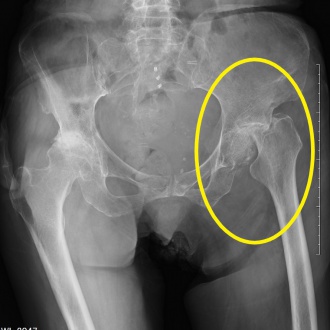

頭の怪我で受診も、大腿骨骨折だった!

頭に大きなたんこぶを認めましたが、転んでから動けなくなりました。全身をMRIやレントゲンで調べたところ、大腿骨の骨折を認めました。頭のMRI検査は異常なく、救急車で総合病院に搬送しました。

レントゲン写真の黄色で囲ったところが骨折した箇所です。